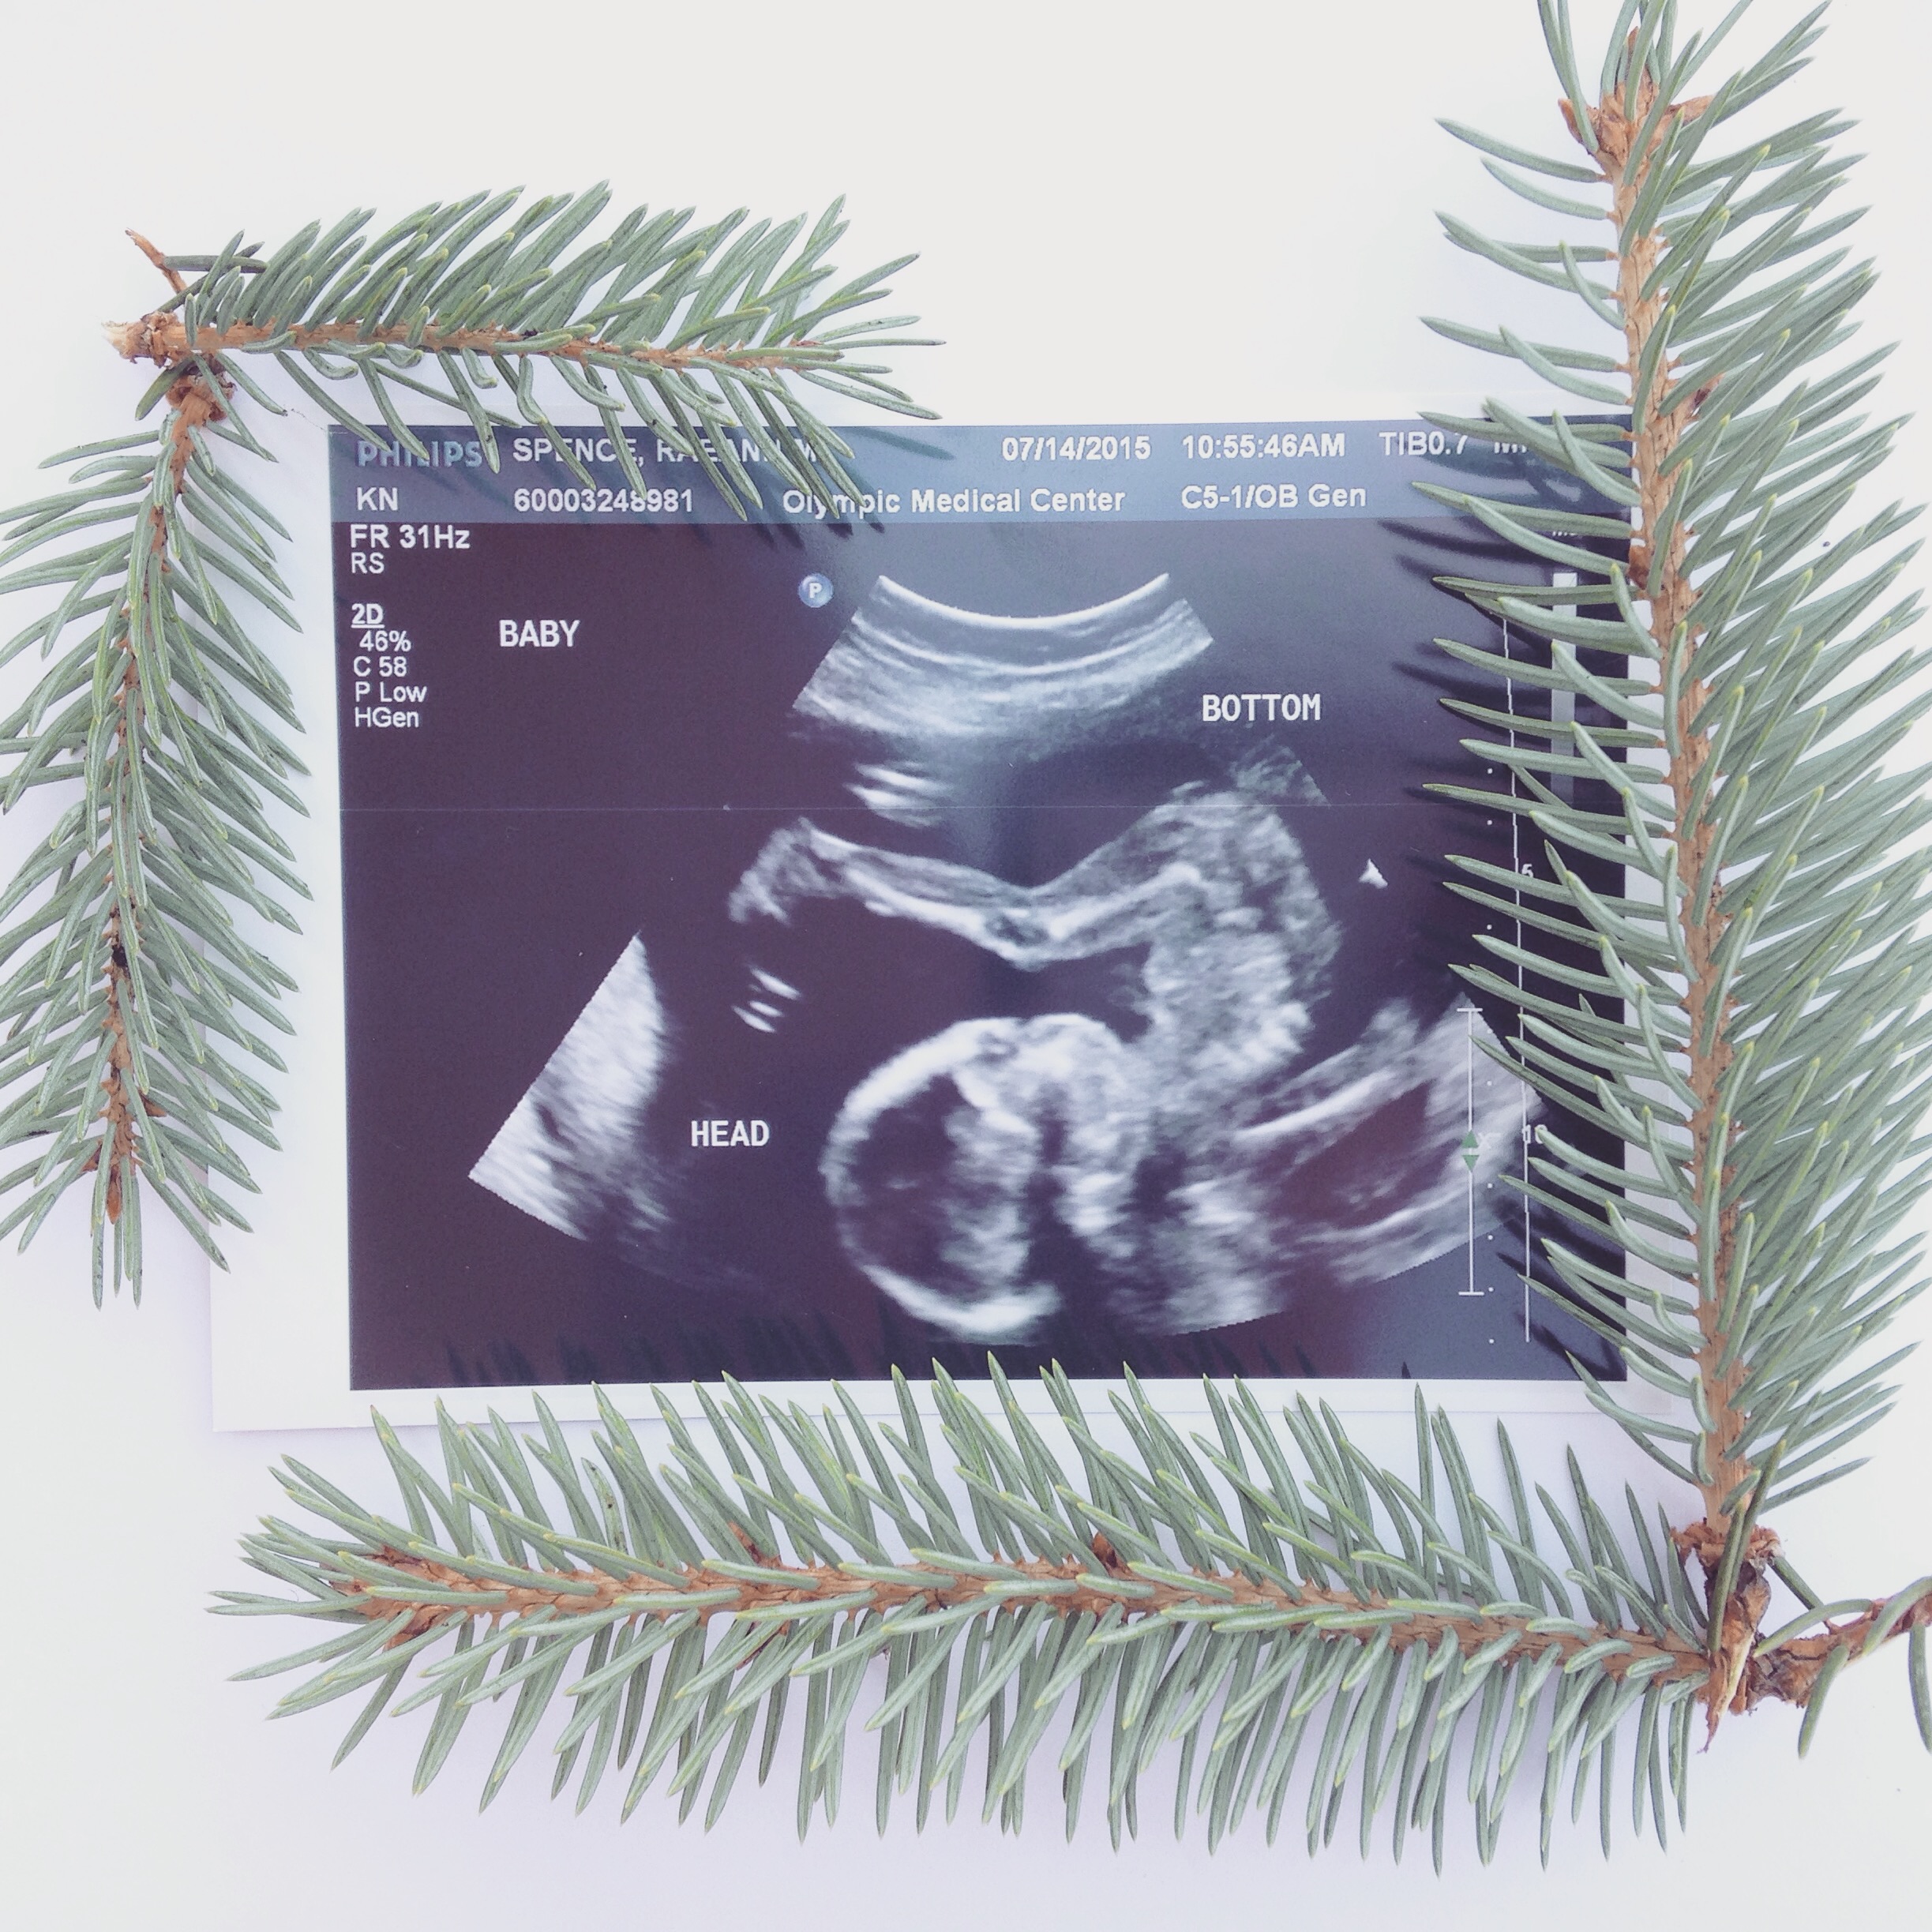

We had our AS today and everything looked great! The tech said if she had seen something unusual she would have told the doctor and they would have talked to me but she said it looked great. She also confirmed it's a GIRL! We had a sneak peak last month and she just confirmed it (good thing because we already bought so many girl clothes while on vacation last week)! LO was all curled up in the bottom of my uterus and there was so much space up top... She was all cozy, moving around and then she got the hiccups! It was hard to get some of the shots thought because she was curled up so I had to go into all kinds of positions... Ouch! So worth it though!